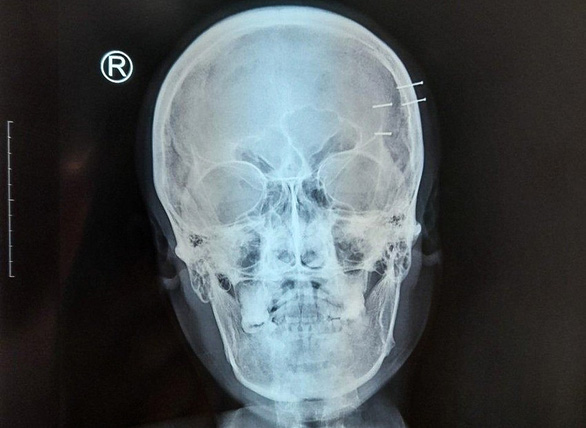

Phim X-quang cho thấy 4 cây đinh ghim vào thái dương bên trái của anh H. - Ảnh: CTV

Sau khi chụp X-quang, các bác sĩ xác định có 4 cây đinh nhỏ, dài khoảng 1,5cm nằm ở vùng thái dương bên trái của bệnh nhân. Các cây đinh được xác định không vào não của bệnh nhân nên bác sĩ phẫu thuật, lấy các dị vật ra khỏi hộp sọ.